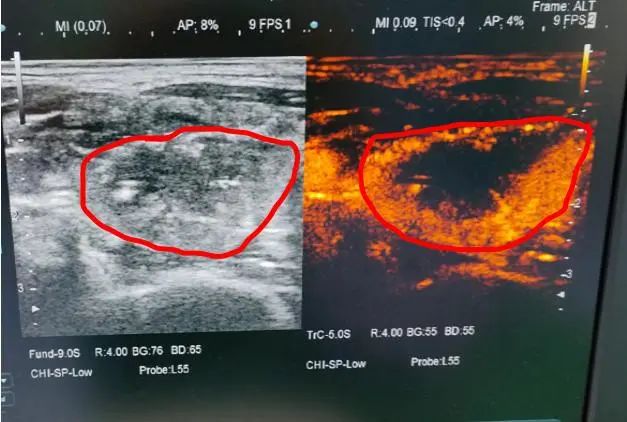

消融后造影大部分组织无血供